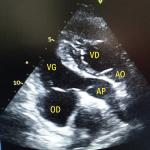

Tachycardie atriale focale

Un homme de 26 ans, militaire, consulte dans le cadre de sa visite de contrôle périodique d’aptitude au parachutisme...